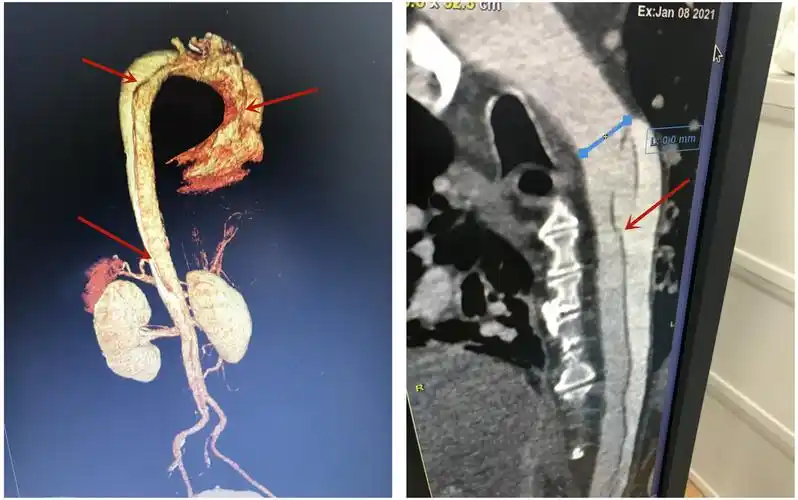

患者,男,56岁,发现腹部肿块7天,主动脉cta腹主动脉巨大真性动脉瘤合并

术前主动脉cta